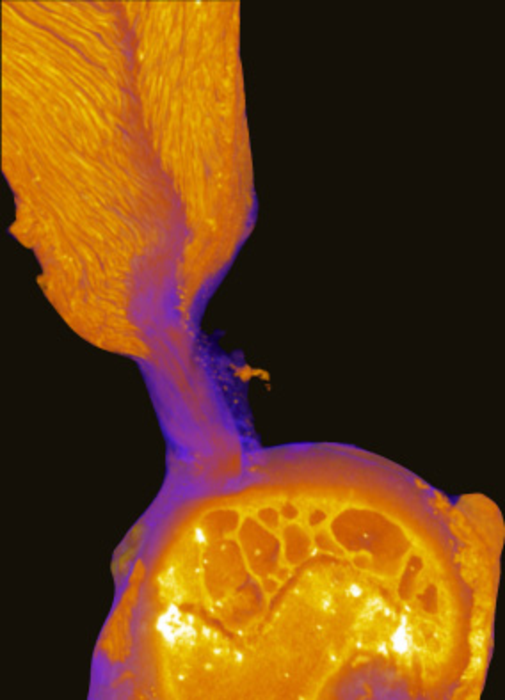

To take a closer look at the enthesis, or the transitional material where each of the four rotator cuff tendons attaches to the bone, the team applied a novel micro computed tomography (microCT) technique. The images revealed a hidden site in the supraspinatus tendon enthesis of mouse shoulders where tendon fibers directly inserted into bone over about 30% of the well-known attachment footprint. Through biomechanical analysis, coupled with numerical simulations, they found that the toughness of the healthy rotator cuff arises from the composition, structure and position of the enthesis as the architecture of the fibrous soft tissues interacts with that of the bone. It was the first time researchers have been able to see both the soft and hard tissues in the rotator cuff simultaneously.

“When [lead author] Mikhail Golman first showed us these images, we realized that much of the old picture of how tendon and bone interact had to be redrawn,” Genin said. “The fiber system there seems like fibers in a rope, and we can understand much about where the toughness comes from by understanding how these fibers break sequentially when they are next to the bone. It’s a new way of thinking about how to attach different materials.”